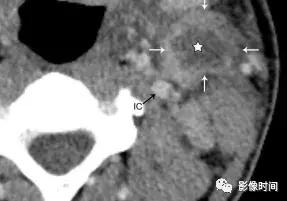

增强 CT 显示左侧颈深淋巴结环形强化 (白色箭头),伴液化性坏死 (星形),左颈内动脉 (IC) 受压后内移位。3 天后显示化脓性淋巴结破裂 (箭头),注意正常的右侧颈动脉间隙保留的脂肪间隙 (圆圈)。化脓性淋巴结破裂,液体渗入到颈动脉间隙 (箭头)。